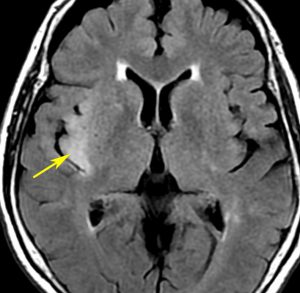

右側頭葉島の病変です。1年間の経過ではっきり増大したので,無症状でしたが生検術を行いました。病理組織では,異型グリアの増殖はありましたが,核分裂蔵,血管内皮の増生や壊死は明らかではありませんでした。しかし,遺伝子診断ではIDH1/2 野生型,ATRX retained,TERT promotor野生型,1p/19q共欠失なしでした。膠芽腫という確定病理診断です。

標準治療を加えましたが,数ヶ月後に急激な増大を呈しました。グレード4の臨床像です。MRI画像よりも病理組織像よりも,遺伝子診断の方がより性格に予後を示す例です。